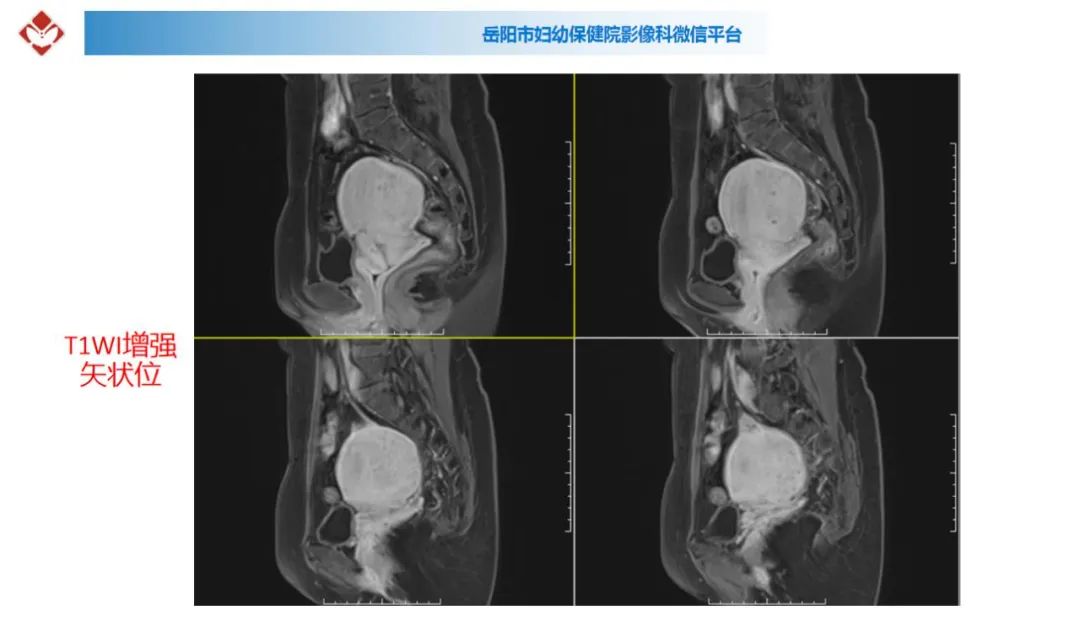

典型疑难病例讨论

来源:岳阳市妇幼保健院影像科